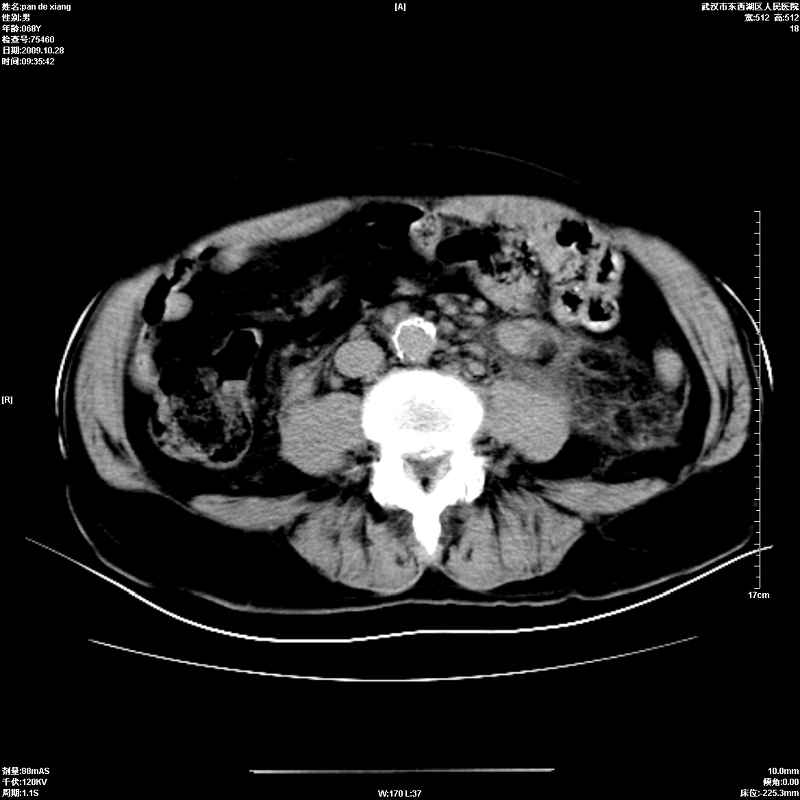

以下是引用杀毒软件在2009-10-28 20:41:00的发言:[br]结合临床考虑---白血病双肾改变或淋巴瘤。

以下是引用zxl51642在2009-10-29 9:59:00的发言:[br]结合临床“单克隆免疫球蛋白血症”,考虑双肾为继发损害并肾功能不全(尿中大量igg及少量iga、igm等大分子免疫球蛋白滤出所致继发损害),椎前软组织肿块为髓外造血。与浆细胞瘤有区别,平扫时有战友说的很清楚。